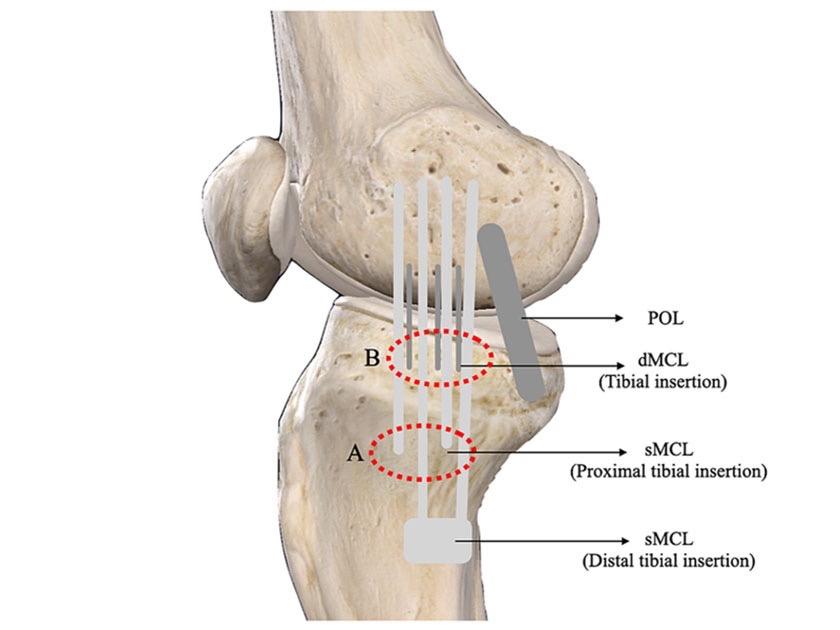

看懂【内侧副韧带】内侧副韧带,膝关节内侧稳定的核心。抵抗膝关节外翻应力,限制胫骨外旋。